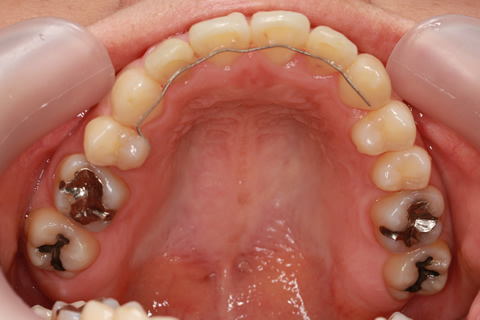

受け口(反対咬合)の症例

症例一覧